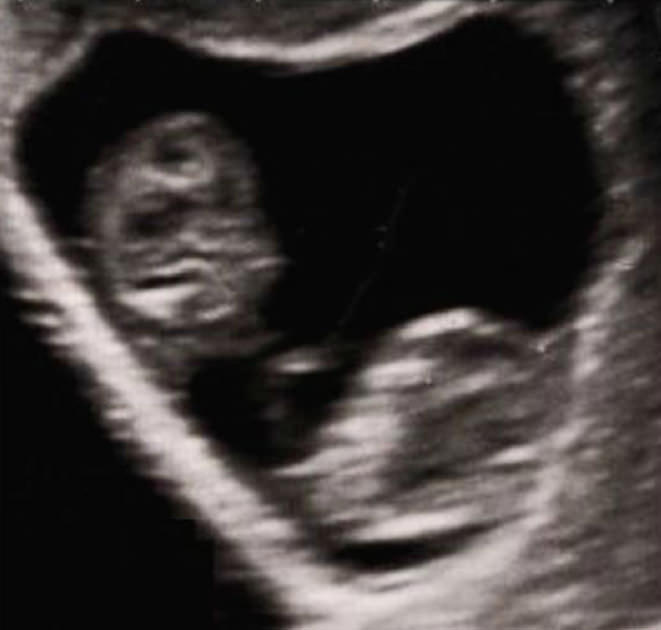

אבל כשהלכו לאולטרסאונד נוסף, הם היו בשוק.

ברחם, מאחורי התאומים, הרופא ראה פרצופים נוספים. מסתבר ששרלין שלא יכלה להיכנס להריון, בהריון עכשיו עם רביעייה!